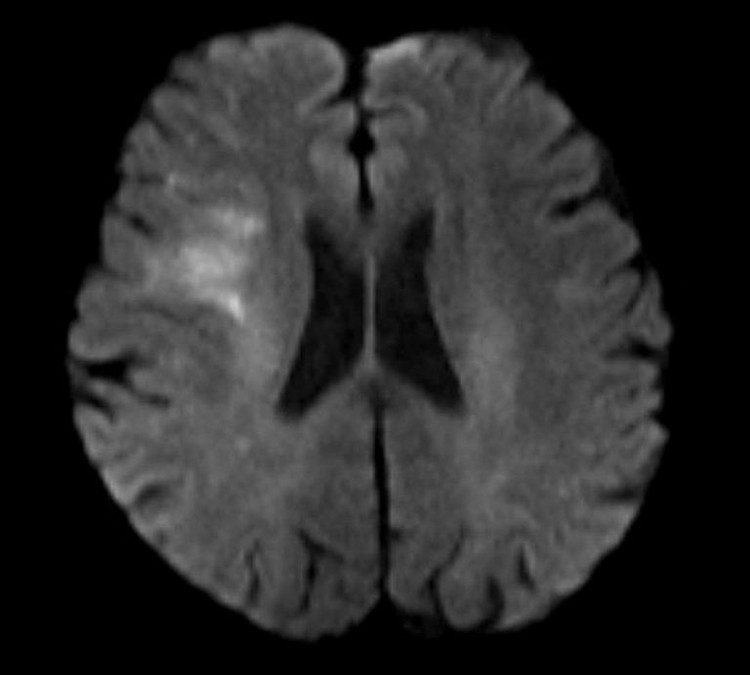

dot-quy-do-cao-1.jpg

dot-quy-do-cao-2.jpg

Hình MRI bệnh nhân T.L bị đột quỵ - Ảnh BVCC